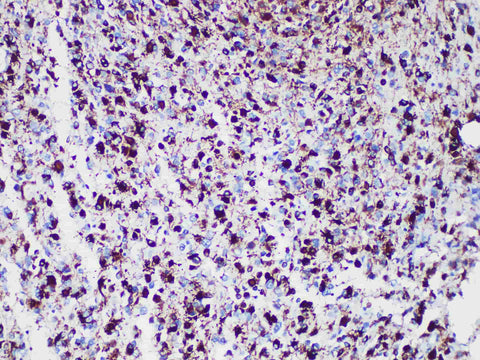

GFAP Monoclonal Antibody stored at 2~8°C

Applications IHC-P

Tissue Specificity Glioma

Glial Fibrillary Acidic Protein(GFAP) is a kind of intermediate silk protein with a molecular weight of about 50 kDa. In the central nervous system, GFAP is expressed in astrocytes and ependymal cells, but not in other glial cells. However, it may be expressed in some immature oligodendrocytes and choroid plexus cells. GFAP is also expressed in Schwann cells and satellite cells of sensory ganglia in peripheral nervous system, and in myoepithelial cells and chondrocytes. In tumor tissue, GFAP is expressed in astrocytoma, ependymoma, malignant glioma, oligodendrocytoma and Schwann cell tumor. In most cases, chondroma, chondrosarcoma and pleomorphic adenoma also showed GFAP positive. This marker is mainly used to judge glioma and metastasis.